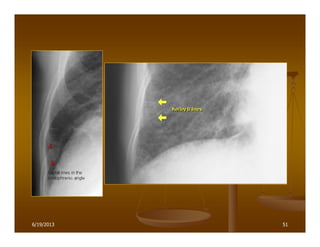

516/19/2013

Dày vách liên tiểu thùy

6/19/2013